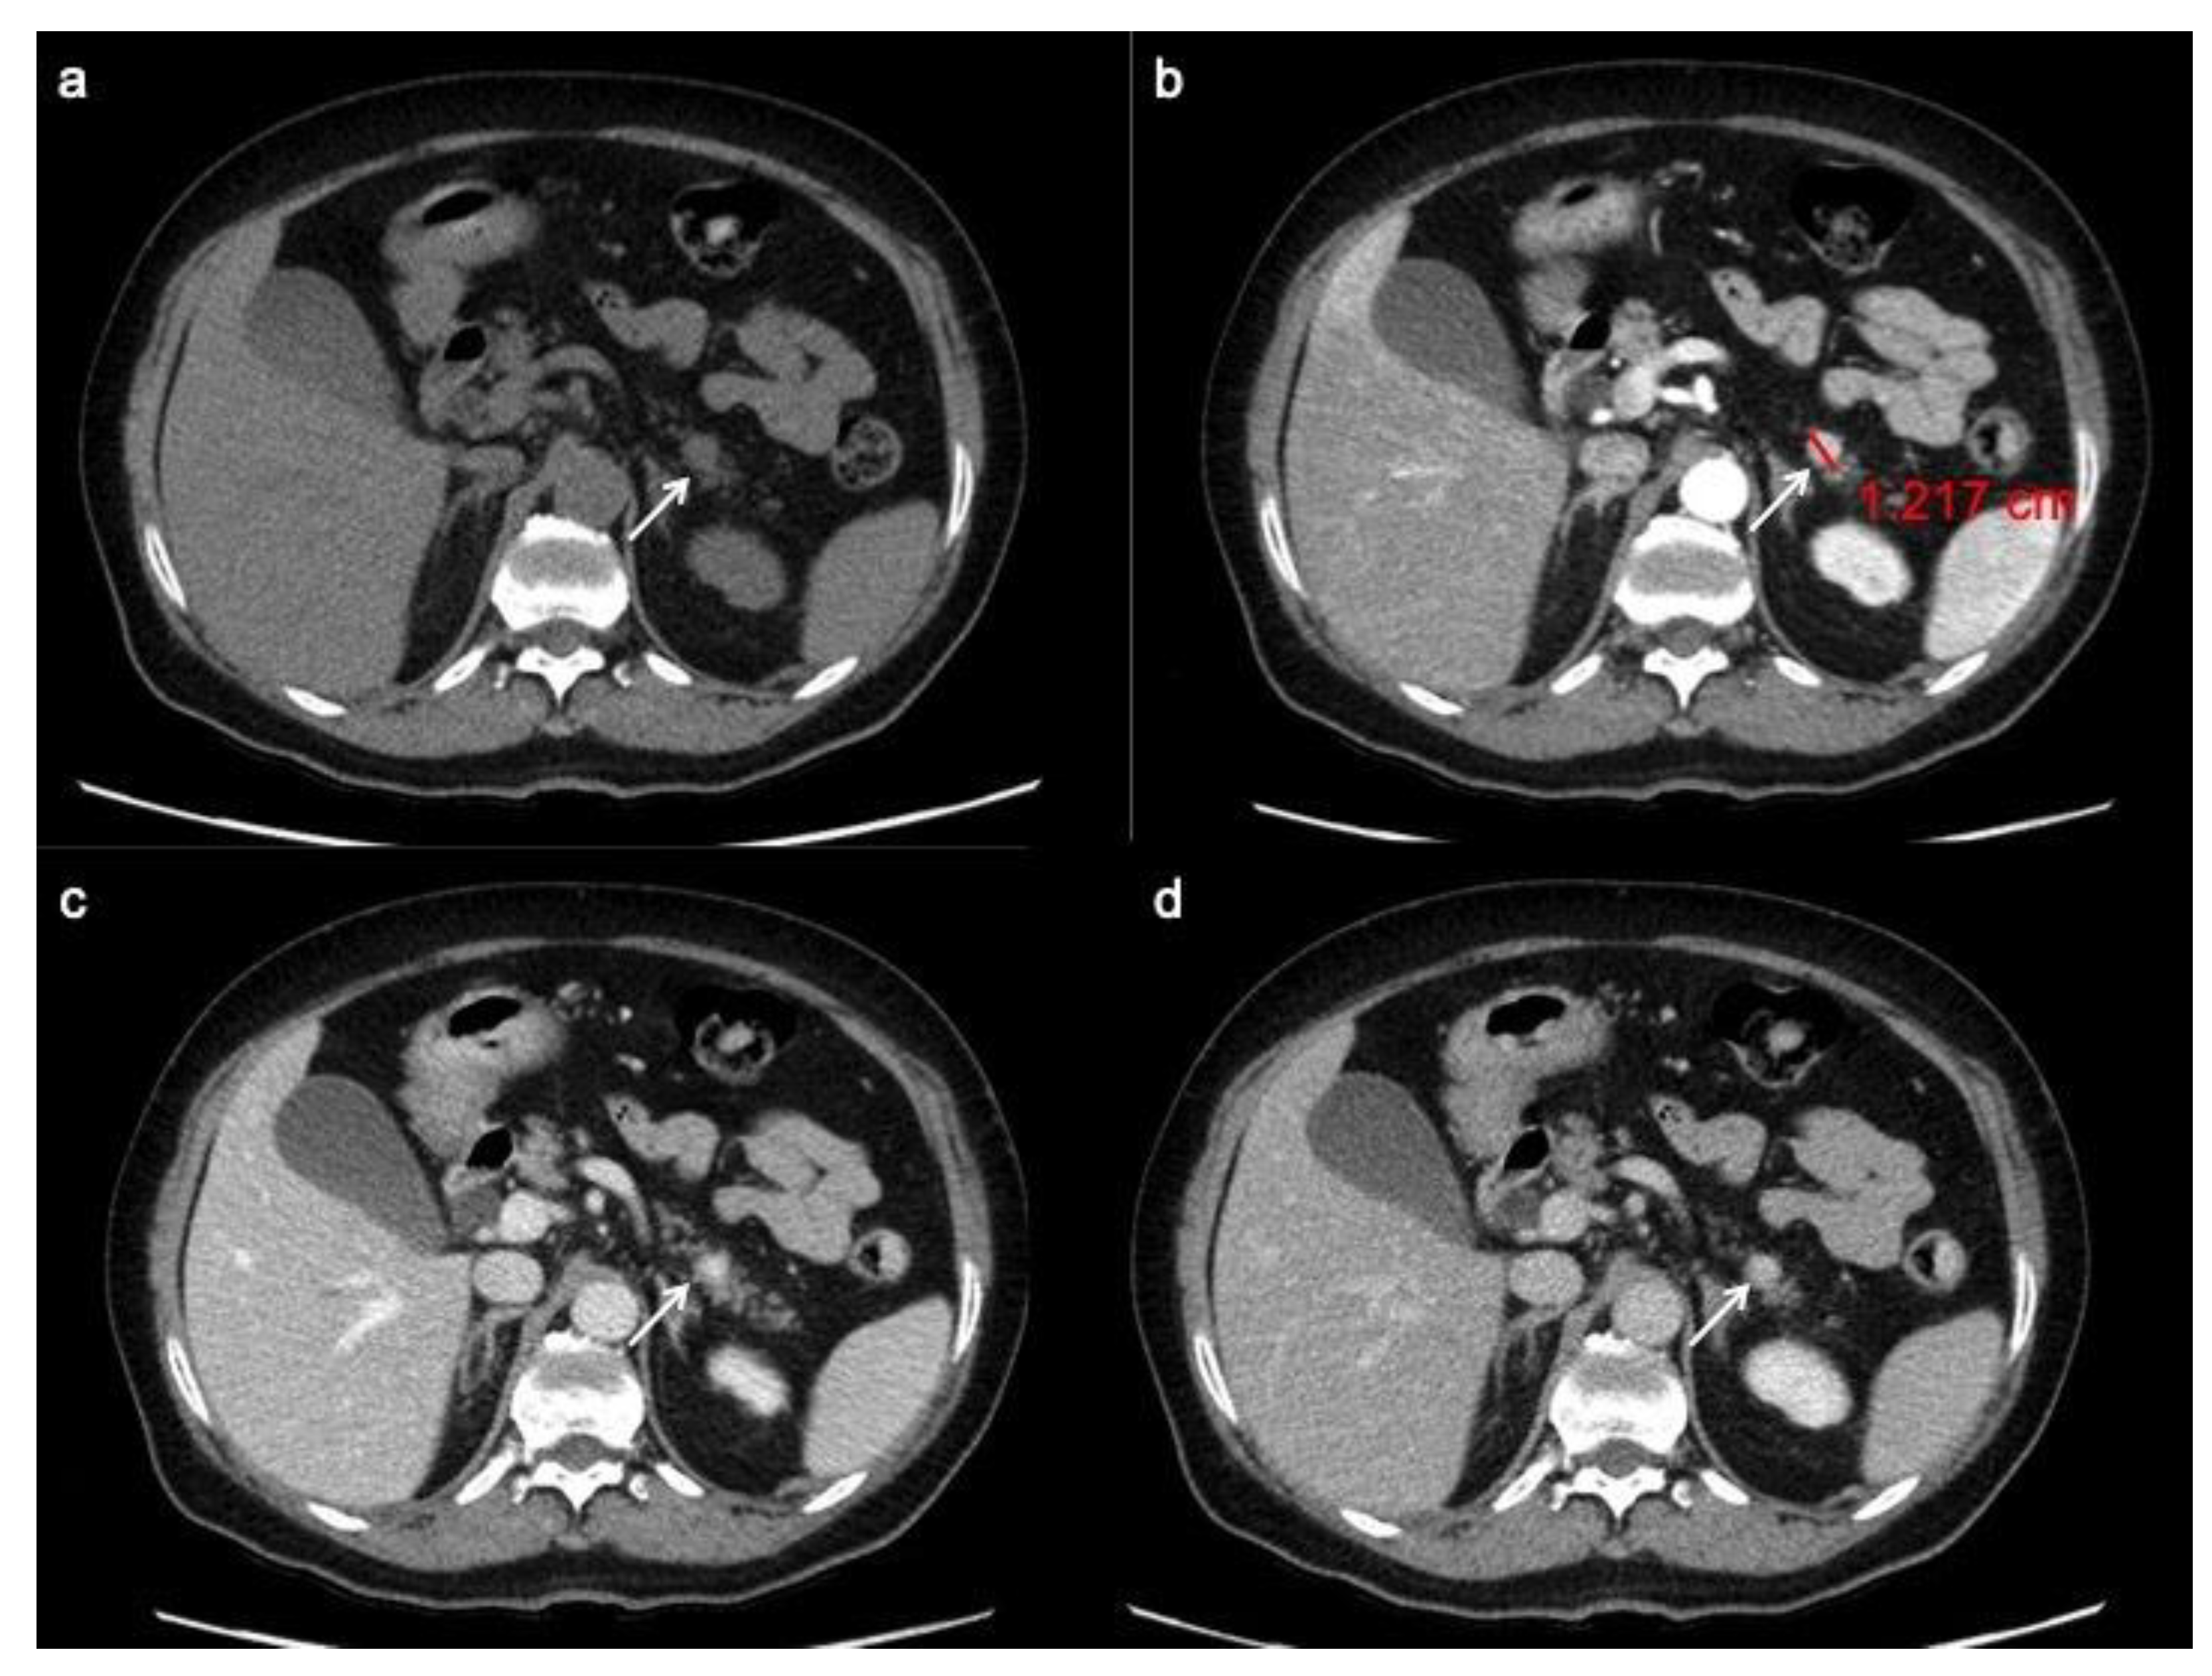

At pre-contrast CT examination, panNENs typically appear as well-rounded, isodense or slightly hypo-dense lesions, with a homogeneous pattern and regular margins [28]. Following the administration of intravenous contrast material, panNENs typically tend to hyper-enhance during arterial phase and demonstrate a slow washout, appearing hyper-dense or isodense among the surrounding parenchyma during portal phase (Figure 1) [29,30]. This typical presentation is more frequently seen in functioning tumors; non-functioning panNENs, especially large ones, more often tend to have an atypical appearance.

Figure 1.

PanNET G1 according to the 2019 WHO classification. CT images in the transverse plane during the basal (a), the arterial (b), the portal venous (c) and the delay (d) phases show a small pancreatic hypervascularized tumor of the pancreatic tail with sharp margin (arrow).